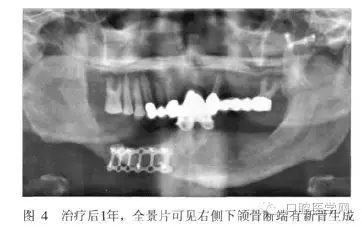

術(shù)后2周和半年進行兩次重襯。治療后半月、3月、6月、1年后復(fù)診,患者的頜面部外貌明顯改善,咀嚼功能提高,義齒使用效果良好(圖3)。全景片示骨斷端有新骨生成(圖4)。

從患者修復(fù)后1年的效果來看,義齒臨床效果良好,X線片示斷端骨密度升高。筆者認(rèn)為對于類似長期骨愈合不良的斷端,通過適宜的功能刺激及義齒功能狀態(tài)下維持骨斷端的穩(wěn)定,可能有利于促進骨的生長和愈合。